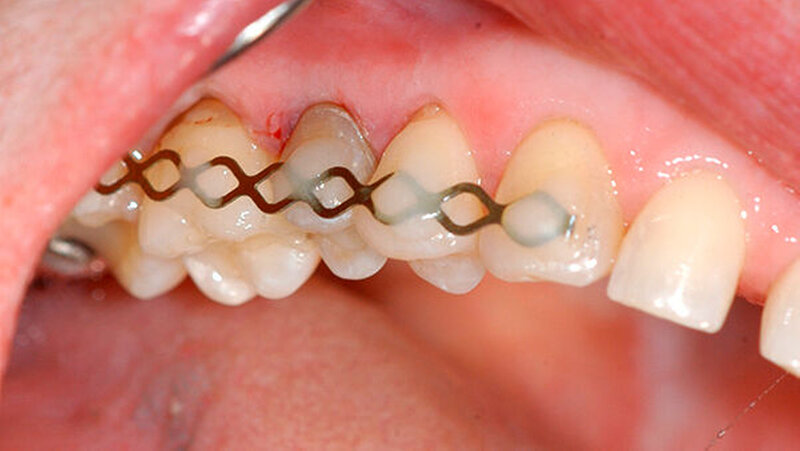

Die retrograde Präparation und der Frakturspalt wurden mit Biodentine aufgefüllt (Abbildung 7). Während des initialen Aushärtens des Zements wurde die restliche Wurzeloberfläche kontinuierlich mit der Nährlösung der Zahnrettungsbox versorgt. Nach etwa 15 Minuten Aushärtungszeit konnte der Zahn replantiert und im Anschluss für zehn Tage mit einer TTS-Schiene (TTS; Medartis, Basel) semirigide geschient werden (Abbildung 8). Kontrollen nach zehn Tagen, drei und sechs Monaten zeigten einen symptomlosen Zahn sowie eine unauffällige Perkussionsprobe ohne Anzeichen einer Ankylose und physiologische Taschensondierungstiefen von 3 mm (Abbildung 9).